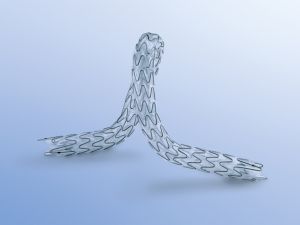

1. Ουρητηρική ενδοπρόθεση (URS) για Παλίνδρομη ή Ορθόδομη χρήση

2. Ενδοπρόθεση βολβικής ουρήθρας

3. Ενδοσκοπική τριγωνική ενδοπρόθεση (TPS) από Nitinol για προστατική ουρήθρα

4. Ενδοπρόθεση για στένωση του αυχένα της κύστης (RPS)

1. Ουρητηρική ενδοπρόθεση (URS) για Παλίνδρομη ή Ορθόδομη χρήση

2. Ενδοπρόθεση βολβικής ουρήθρας

3. Ενδοσκοπική τριγωνική ενδοπρόθεση (TPS) από Nitinol για προστατική ουρήθρα

4. Ενδοπρόθεση για στένωση του αυχένα της κύστης (RPS)